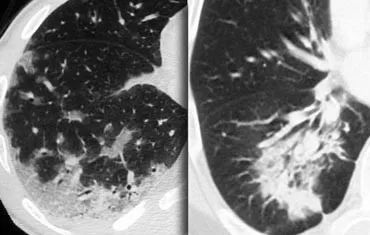

下图2例为隐源性机化性肺炎(COP)的慢性实变。

胸膜下及周围分布有斑片状实变,鉴别诊断与上述相同。

在慢性嗜酸粒细胞性肺炎中,也会有嗜酸性粒细胞增多。

在纤维化方面,还会出现其他纤维化症状,如蜂窝状或牵张性支气管扩张。

支气管肺泡癌也可以这样。

机化性肺炎(OP),是一种炎症,愈合过程的特点是渗出物的机化和愈合,而不是溶解和吸收。

如果不能确定病因,则称为隐源性组织性肺炎(COP)。

在早期被描述为毛细支气管炎-闭塞性组织性肺炎(BOOP)。

COP患者通常有几个月的咳嗽病史。

许多病例为特发性,但OP也可在肺部感染、药物反应、胶原血管疾病、韦格纳肉芽肿病和吸入有毒烟雾后出现。

下图是慢性嗜酸细胞性肺炎。

这是一位低度发热、进行性呼吸急促和胸部X线异常的病人。

外周血嗜酸性粒细胞明显增多。

就像COP一样,我们看到胸膜下分布的斑片状实变。

慢性嗜酸粒细胞性肺炎是一种特发性疾病,主要由嗜酸性粒细胞组成,其特征是肺泡内充满大量的嗜酸性粒细胞。

慢性嗜酸粒细胞性肺炎通常与外周血嗜酸性粒细胞增多有关,患者对类固醇治疗反应迅速。